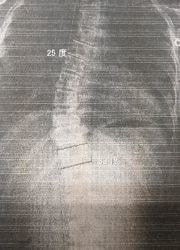

レントゲンのビフォーアフター)

写真1(施術前) 写真2(5か月後)

○コブ角上27度⇒25度(2度改善)、下40度⇒33度(7度改善)

※コブ角は専門医の診断

施術19回:コブ角33度

施術前:コブ角40度